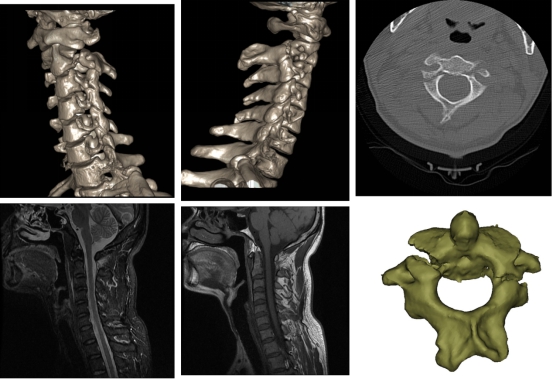

图2 患者周某术前影像学资料

9.3日确定手术方案、手术时间、手术人员等安排;拟9.4给患者周某进行“颈2骨折切开复位椎弓根钉系统内固定术”,拟9.5日给患者李某行“髋臼骨折切开复位内固定、胸12骨折切开复位内固定术”。

9.4日患者周某手术顺利完成;9.5日患者李某手术顺利完成。

9.7日复查术后X片,患者李某可在床上自由翻身,患者周某恢复正常活动。